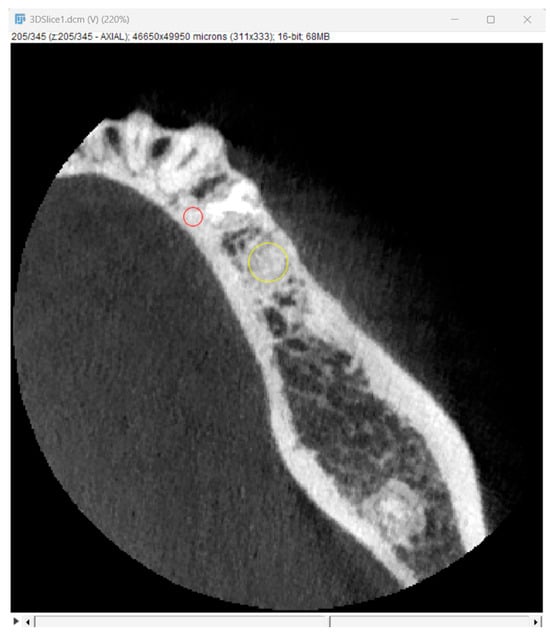

Bone optical density was measured in Hounsfield units (HU) using ImageJ software (version 1.53k, Wayne Rasband and contributors, National Institutes of Health, Kensington, MD, USA). The readings were taken on the horizontal plane in the central part of the alveoli 7 days and 6 months after surgery (Figure 5). If an interradicular septum was present in the central part of the socket, measurements were taken more coronally to reduce the risk of bias.

Figure 5.

Radiographic optical density of bone measured using ImageJ software. The yellow circle represents the ROI where the measurements were taken, and the red circle represents the positioning pin used for orientation during the measurements.

3.2. Optical Bone Density Measurement

The optical density measurements were performed on 10 consecutive cross-sections selected from the central portion of the alveolus in each patient. The measurements were made for representative regions of interest (ROIs) in the augmented site. The data obtained are presented in Table 2.

Table 2.

Mean optical bone density levels in Hounsfield units.

It is worth noting that in the allograft group, the mean optical density increased from 1341.40 to 1499.94 HU. However, the difference was statistically insignificant; therefore, one may only conclude that there was a growth tendency. In contrast, in the xenograft group, the mean optical density increased from 1288.58 to 1881.08 HU, which was statistically significant at p = 0.004.